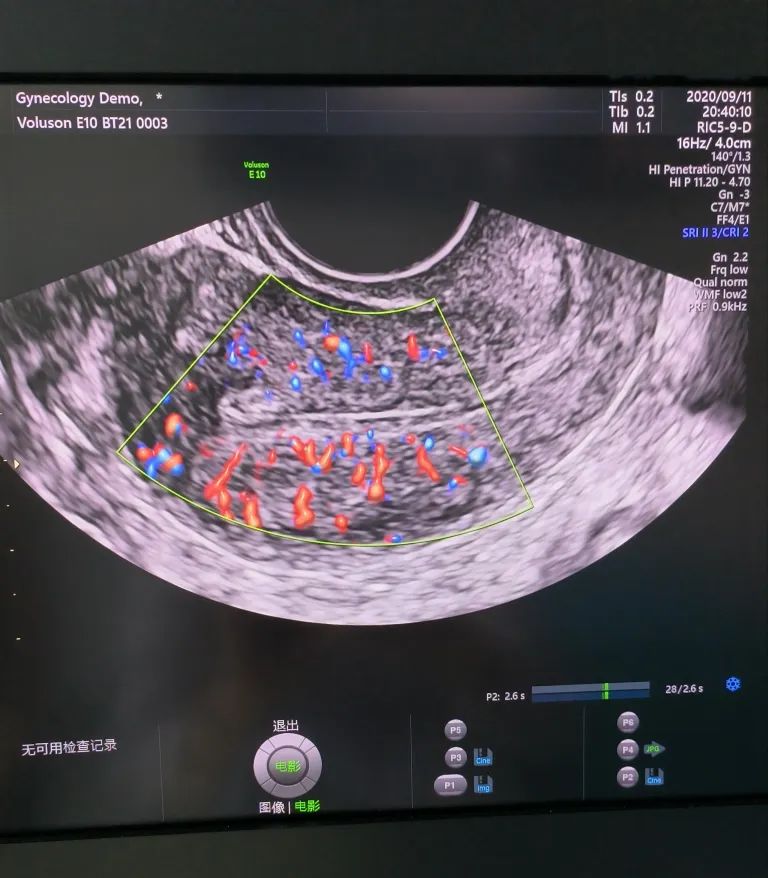

經(jīng)陰道超聲是在陰道超聲探頭上套上避孕套,將探頭伸入陰道進(jìn)行檢查。由于探頭位置接近子宮和卵巢,圖像更清晰,檢查結(jié)果更準(zhǔn)確。而且不需要憋尿,相對(duì)節(jié)省時(shí)間。所以現(xiàn)在大部分醫(yī)院對(duì)有性生活史的婦女更愿意開(kāi)展經(jīng)陰道超聲檢查。